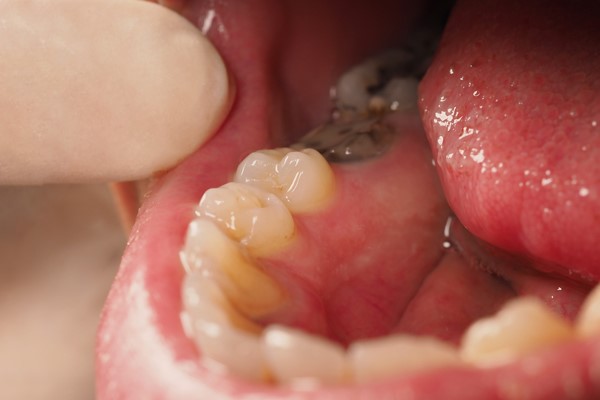

Cavities are damaged areas where small gaps form in the tooth enamel. They result from bacterial activity in the mouth. Cariogenic bacteria produce acid that can demineralize tooth enamel from residues of starchy or sugary foods.

3. Removal of Decayed Tissue: The dentist removes the affected tissue, and after removal, reconstruction takes place.

4. Filling, Sealing, or Blocking: After cleaning the decay, the void left in the tooth must be filled with a biocompatible material. Usually, this material is composite, and it is shaped to restore the anatomy of the decayed part. This material hardens with light (light-curing or light-activated lamps).